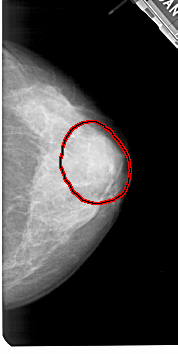

A_1425_1.RIGHT_MLO

RIGHT_MLO LINES 5491 PIXELS_PER_LINE 2806 BITS_PER_PIXEL 12 RESOLUTION 43.5 OVERLAY

FILE: A_1425_1.RIGHT_MLO.OVERLAY

TOTAL_ABNORMALITIES 1

ABNORMALITY 1

LESION_TYPE MASS SHAPE OVAL MARGINS OBSCURED

ASSESSMENT 4

SUBTLETY 3

PATHOLOGY BENIGN

TOTAL_OUTLINES 1

BOUNDARY